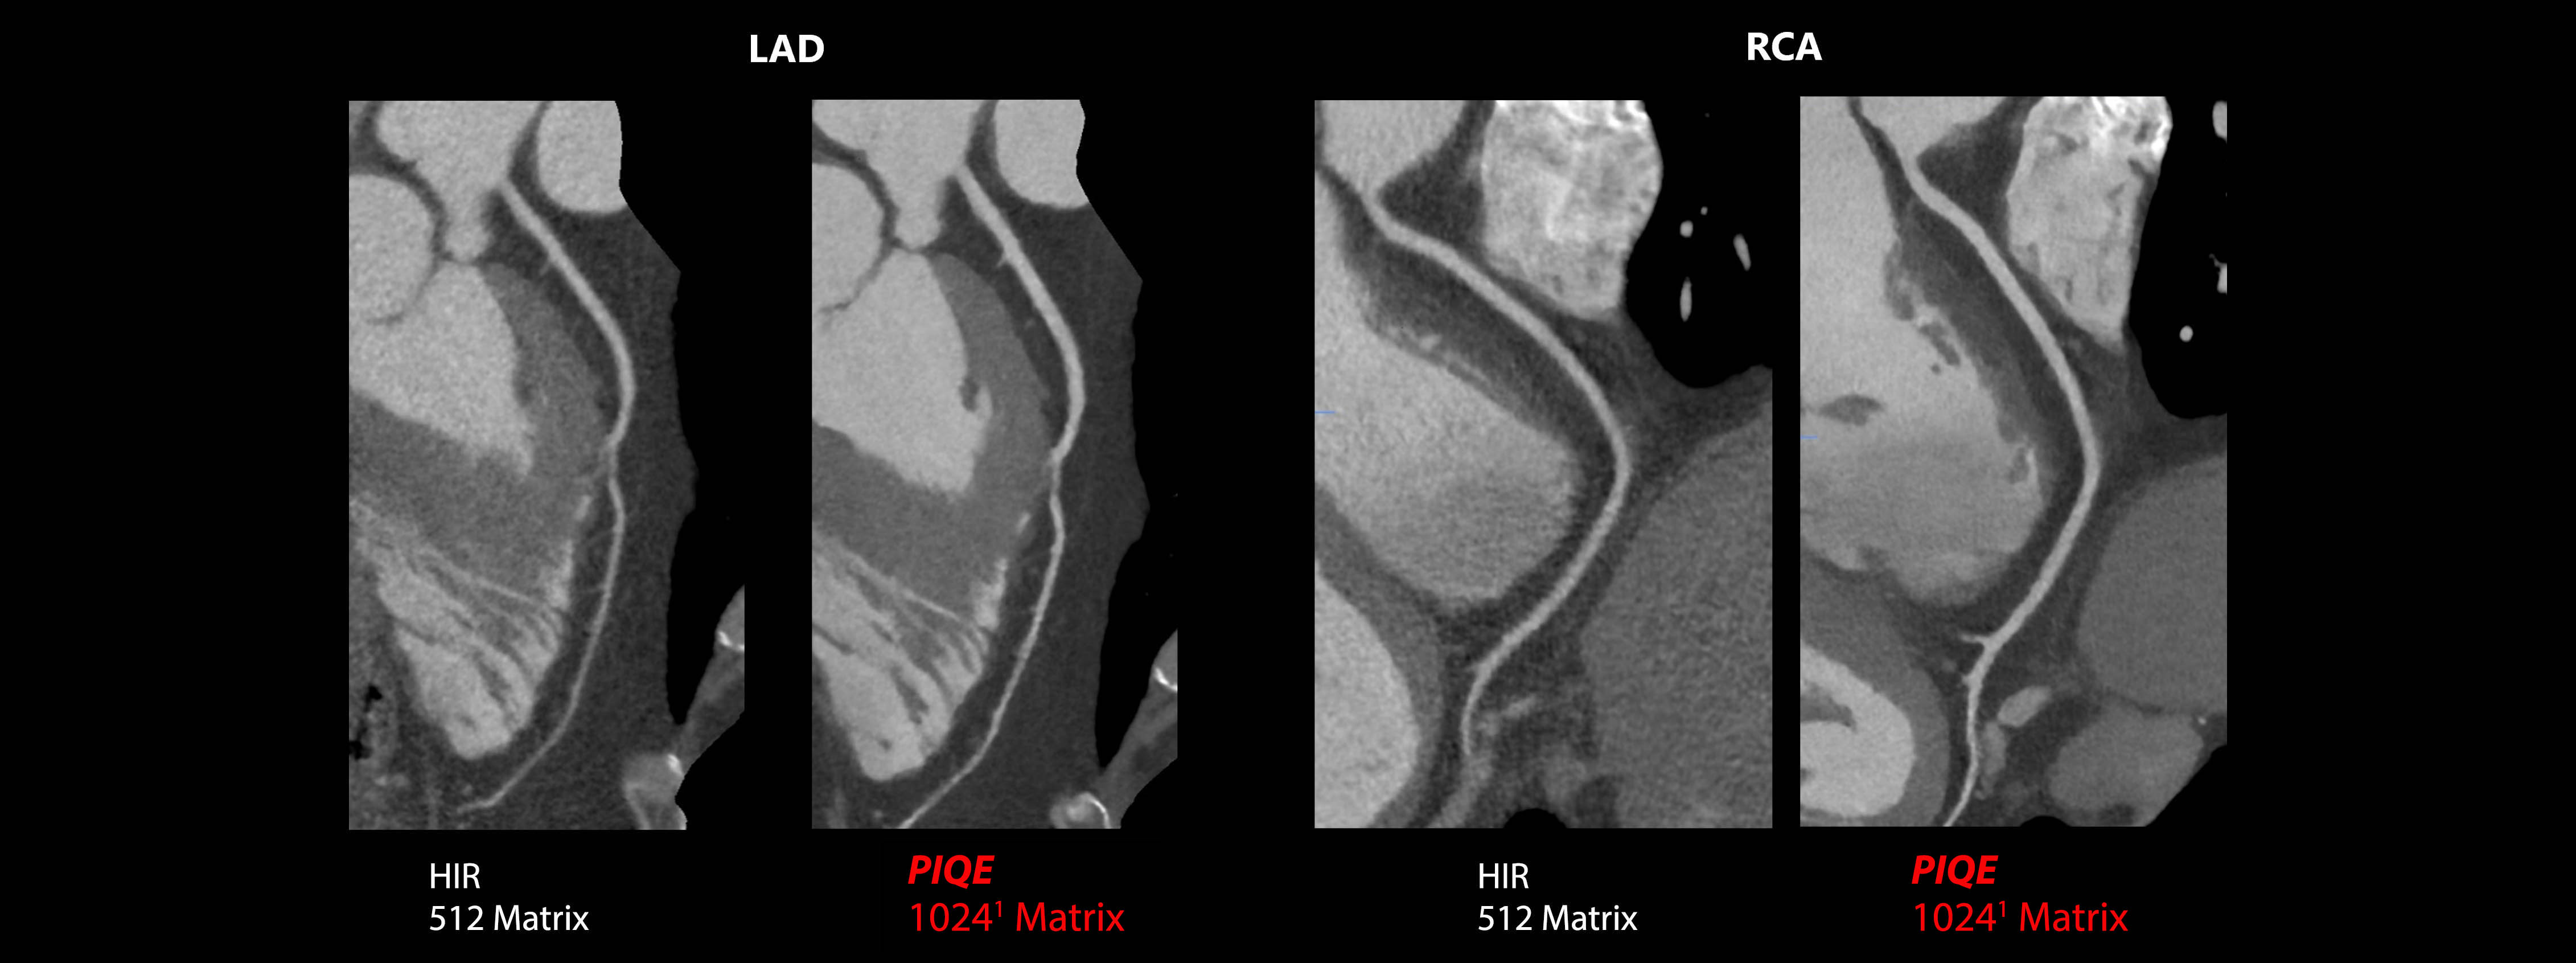

Precise IQ Engine (PIQE) 10241 DLR

Aquilion Serve SP

PIQE1 Super Resolution2 DLR delivers sharp cardiac images without compromising on noise, temporal resolution or dose.

1 Option

2 PIQE is designed to fully utilize the maximum resolution of the detector.

Courtesy Sunshine Coast University Hospital, Australia.

Precise IQ Engine (PIQE) 10241 DLR

Aquilion Serve SP

Improve your diagnostic confidence with PIQE 10241 to reduce cardiac blooming artifacts from calcifications with improved spatial resolution.

1 Option

Courtesy of Steinberg Diagnostic Medical Imaging, USA.

Precise IQ Engine (PIQE) 10241 DLR

Aquilion Serve SP

PIQE1 Super Resolution2 DLR improves diagnostic confidence with sharp cardiac images with improved spatial resolution.

1 Option

Courtesy of Steinberg Diagnostic Medical Imaging, USA.